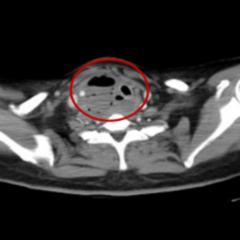

2月15日、2月20日,当长沙沉浸在辞旧迎新的欢声笑语中,两位病情凶险的颈部深部脓肿患者先后被推入耳鼻咽喉头颈外科。他们都有多年糖尿病病史,春节期间饮食不规律、作息紊乱、血糖波动大,让原本隐匿的感染如野火般迅速蔓延。其中一位患者的感染已突破颈部间隙,如藤蔓般向下侵入纵隔区域——那里是心脏、大血管、气管的“交通枢纽”,是人体最脆弱的生命禁区之一。CT影像上,脓肿中密布的气腔像一个个危险的信号,气管严重受压,每一次呼吸都变得艰难。而临床研究数据表明,颈深部脓肿并发下行性纵隔炎,病死率为40%~70%。患者的生命,危在旦夕。

患者甲CT示:颈部及纵隔脓肿,脓肿中含有多个气腔